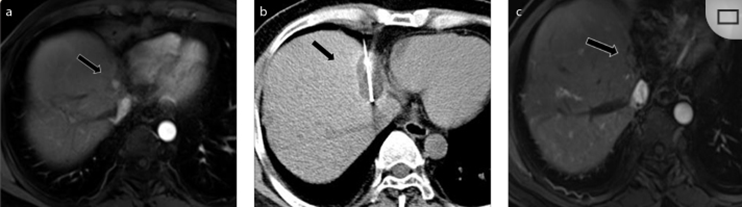

62歲女性,肝轉(zhuǎn)移(卵巢癌)腫瘤的完全消融病例(a)軸向CT顯示病變位置毗鄰心臟和上腔靜脈(黑色箭頭)。(b)術(shù)中軸向CT掃描:使用三個(gè)冷凍探針。1個(gè)月后的軸向(e)和冠狀位(f)增強(qiáng)CT掃描顯示低密度區(qū)域,由于肉芽組織反應(yīng)引起的邊緣增強(qiáng)。